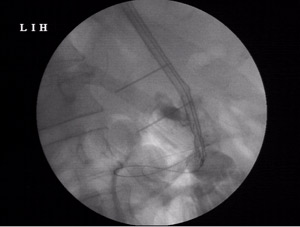

I could pass a wire and dilate the esophago-jejunal anastomosis with placement of a covered metallic self expandeble stent for palliation of dysphagia with half of the covered stent in the j-shaped jejunum and half proximally.

The covered stent will serve to maintain nutrition in this advanced disease .